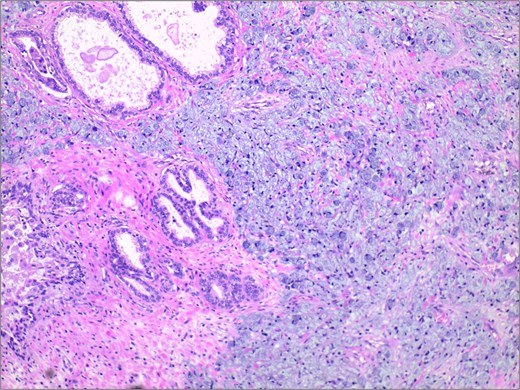

In November 2024, the patient presented with progressive dysuria for 3 years, accompanied by recurrent urinary retention for 3 weeks. Physical examination revealed a prostate enlarged to grade II, with a firm texture, smooth surface, no palpable nodules, no tenderness, a shallow median sulcus, and no sphincter relaxation. Imaging studies with 3.0 T prostate magnetic resonance imaging (MRI) showed a prostate measuring ⁓5.7 × 4.8 × 5.7 cm, with marked enlargement of the transition zone and heterogeneous signals. Small, patchy short T2 signals were internally observed, along with slightly high diffusion-weighted imaging (DWI) signals and slightly decreased apparent diffusion coefficient (ADC) signals, yielding a PI-RADS score of 3. The peripheral zone was thinned and indistinct. The seminal vesicles showed normal size and morphology, and the bladder-seminal vesicle triangle was intact. No enlarged lymph nodes were evident in the pelvic cavity. Laboratory tests showed a total prostate-specific antigen level of 1.759 ng/ml. Initially diagnosed with benign prostatic hyperplasia, the patient underwent transurethral enucleation of the prostate with a thulium laser under general anesthesia on 19 November 2024. The surgery was successful. Postoperative pathology indicated poorly differentiated adenocarcinoma, predominantly signet ring cell carcinoma, presumed to be of gastric origin (Fig. 1). Immunohistochemical analysis revealed negativity for prostate cancer markers (PSA and P504S) and positivity for gastrointestinal tumor markers [CKP(3+), CK20(+), CEA(3+), Villin(2+), CDX-2(2+)] (Fig. 2). Morphological comparison with previous gastric cancer pathology slides showed similar features, confirming metastatic gastric signet ring cell carcinoma to the prostate. The patient continued chemotherapy with the original gastric cancer regimen postoperatively and is currently under follow-up.

Immunohistochemical staining demonstrated strong positivity (++) for villin in the cytoplasm and cell membrane of tumor cells. IHC stain 40×.